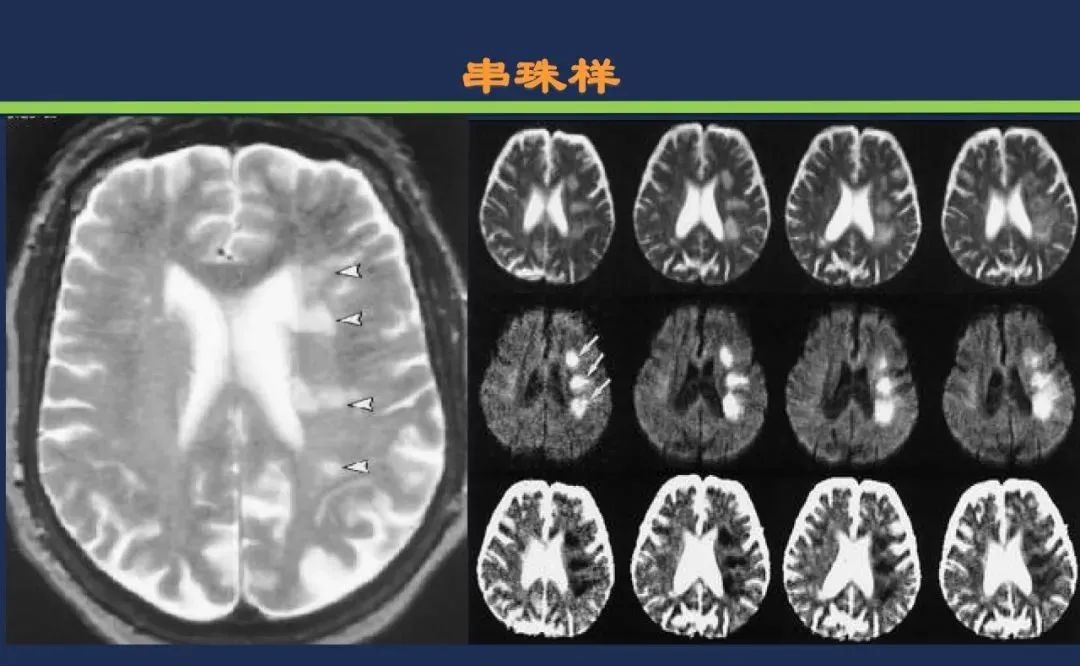

分水岭梗死皮质前型+皮质后型+后上型皮质下前型+皮质下后型+皮质下上型+皮质下外型+皮质下下型